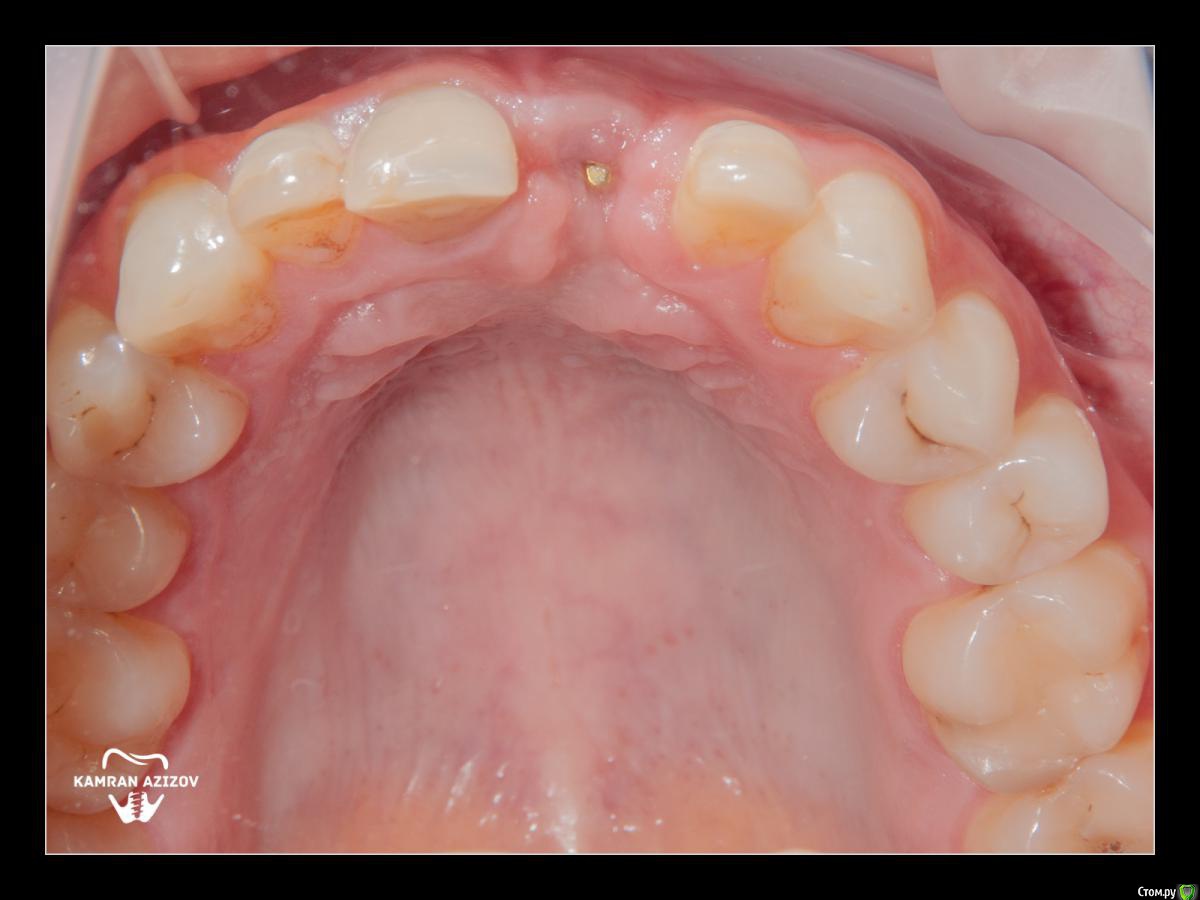

kamranchick Опубликовано 8 октября, 2019 Поделиться Опубликовано 8 октября, 2019 удаление зуба+консервация лунки с вестибулярным ССТчерез 2 месяца имплантация с фдм по карлоссучерез 4 месяца замена на более длинный фдм и широкийпостоянная коронка 5 Ссылка на комментарий